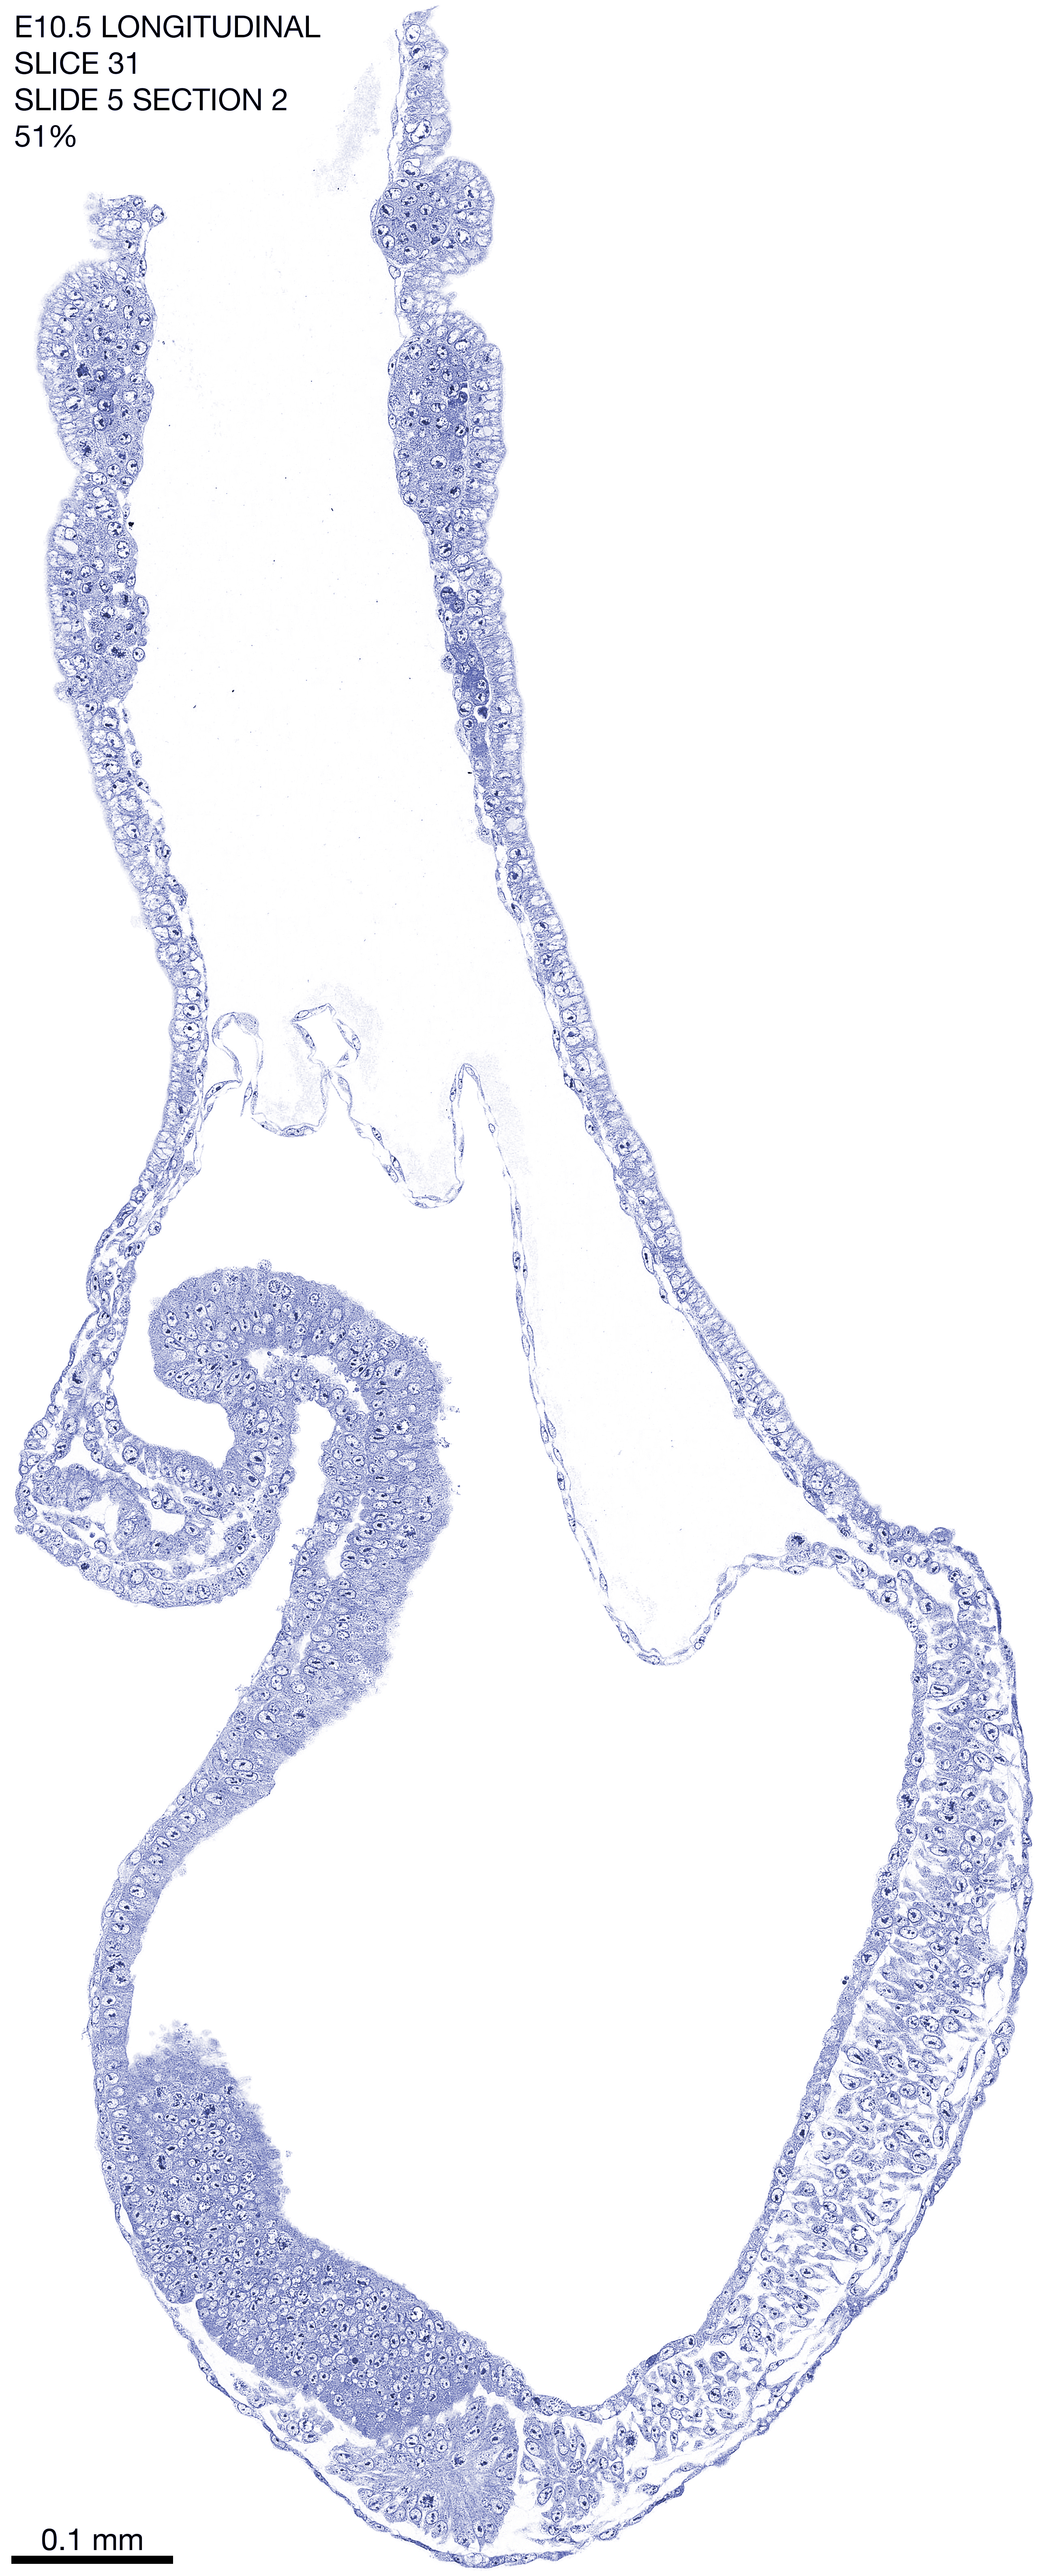

E10.5 Longitudianal Archive This page contains jpg files of ALL SLICES (each 3µm thick) that were scanned of the E10.5 longitudinally cut specimen. Download: Large | High Res Download: Large | High Res Download: Large | High Res Download: Large | High Res Download: Large | High Res Download: Large | High Res Download: Large | High Res Download: Large | High Res Download: Large | High Res Download: Large | High Res Download: Large | High Res Download: Large | High Res Download: Large | High Res Download: Large | High Res Download: Large | High Res Download: Large | High Res Download: Large | High Res Download: Large | High Res Download: Large | High Res Download: Large | High Res Download: Large | High Res Download: Large | High Res Download: Large | High Res Download: Large | High Res Download: Large | High Res Download: Large | High Res Download: Large | High Res Download: Large | High Res Download: Large | High Res Download: Large | High Res Download: Large | High Res Download: Large | High Res Download: Large | High Res Download: Large | High Res Download: Large | High Res Download: Large | High Res Download: Large | High Res Download: Large | High Res Download: Large | High Res Download: Large | High Res Download: Large | High Res Download: Large | High Res Download: Large | High Res Download: Large | High Res Download: Large | High Res Download: Large | High Res Download: Large | High Res Download: Large | High Res Download: Large | High Res Download: Large | High Res Download: Large | High Res Download: Large | High Res Download: Large | High Res Download: Large | High Res Download: Large | High Res Download: Large | High Res Download: Large | High Res Download: Large | High Res